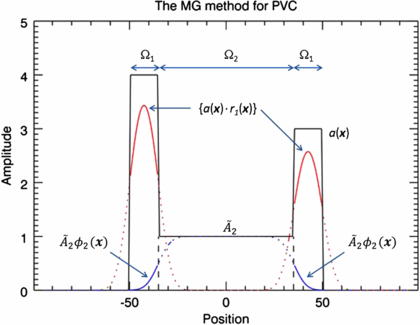

where M is the total number of regions. This method has similarities to scatter and attenuation correction used in PET and SPECT: first there is a subtraction of events that are misplaced into the target region (similar to scatter correction), and then a multiplicative correction is applied for events that are lost from the target region (similar to attenuation correction). The disadvantages with this method are that; (1) the correction is valid only for voxels within the target region, and (2) the true mean values in the background regions  have to be initially estimated. These would typically be obtained from regions large enough that the central part can be assumed to be unaffected by PVE. An alternative would be to use the GTM method to determine the mean values of the background regions, as described in Quarantelli et al (2004). This is known as the modified MGM (mMGM). Figure 3 illustrates MGM applied to a 1D phantom profile.

have to be initially estimated. These would typically be obtained from regions large enough that the central part can be assumed to be unaffected by PVE. An alternative would be to use the GTM method to determine the mean values of the background regions, as described in Quarantelli et al (2004). This is known as the modified MGM (mMGM). Figure 3 illustrates MGM applied to a 1D phantom profile.

Figure 3. Illustration of the MG method (15) (Müller-Gartner et al 1992). The correction is applied only in the target region, Ω1. Spill-in correction is done by subtracting a background term  . Spill-out correction is achieved by dividing by r1(x). The true mean value,

. Spill-out correction is achieved by dividing by r1(x). The true mean value,  , in the background region, Ω2, has to be initially estimated. The black solid line represents the true distribution. The red and blue lines represent the result of convolving the target and background regions separately by the PSF. The solid portion of these curves represents the data used in the algorithm.

, in the background region, Ω2, has to be initially estimated. The black solid line represents the true distribution. The red and blue lines represent the result of convolving the target and background regions separately by the PSF. The solid portion of these curves represents the data used in the algorithm.